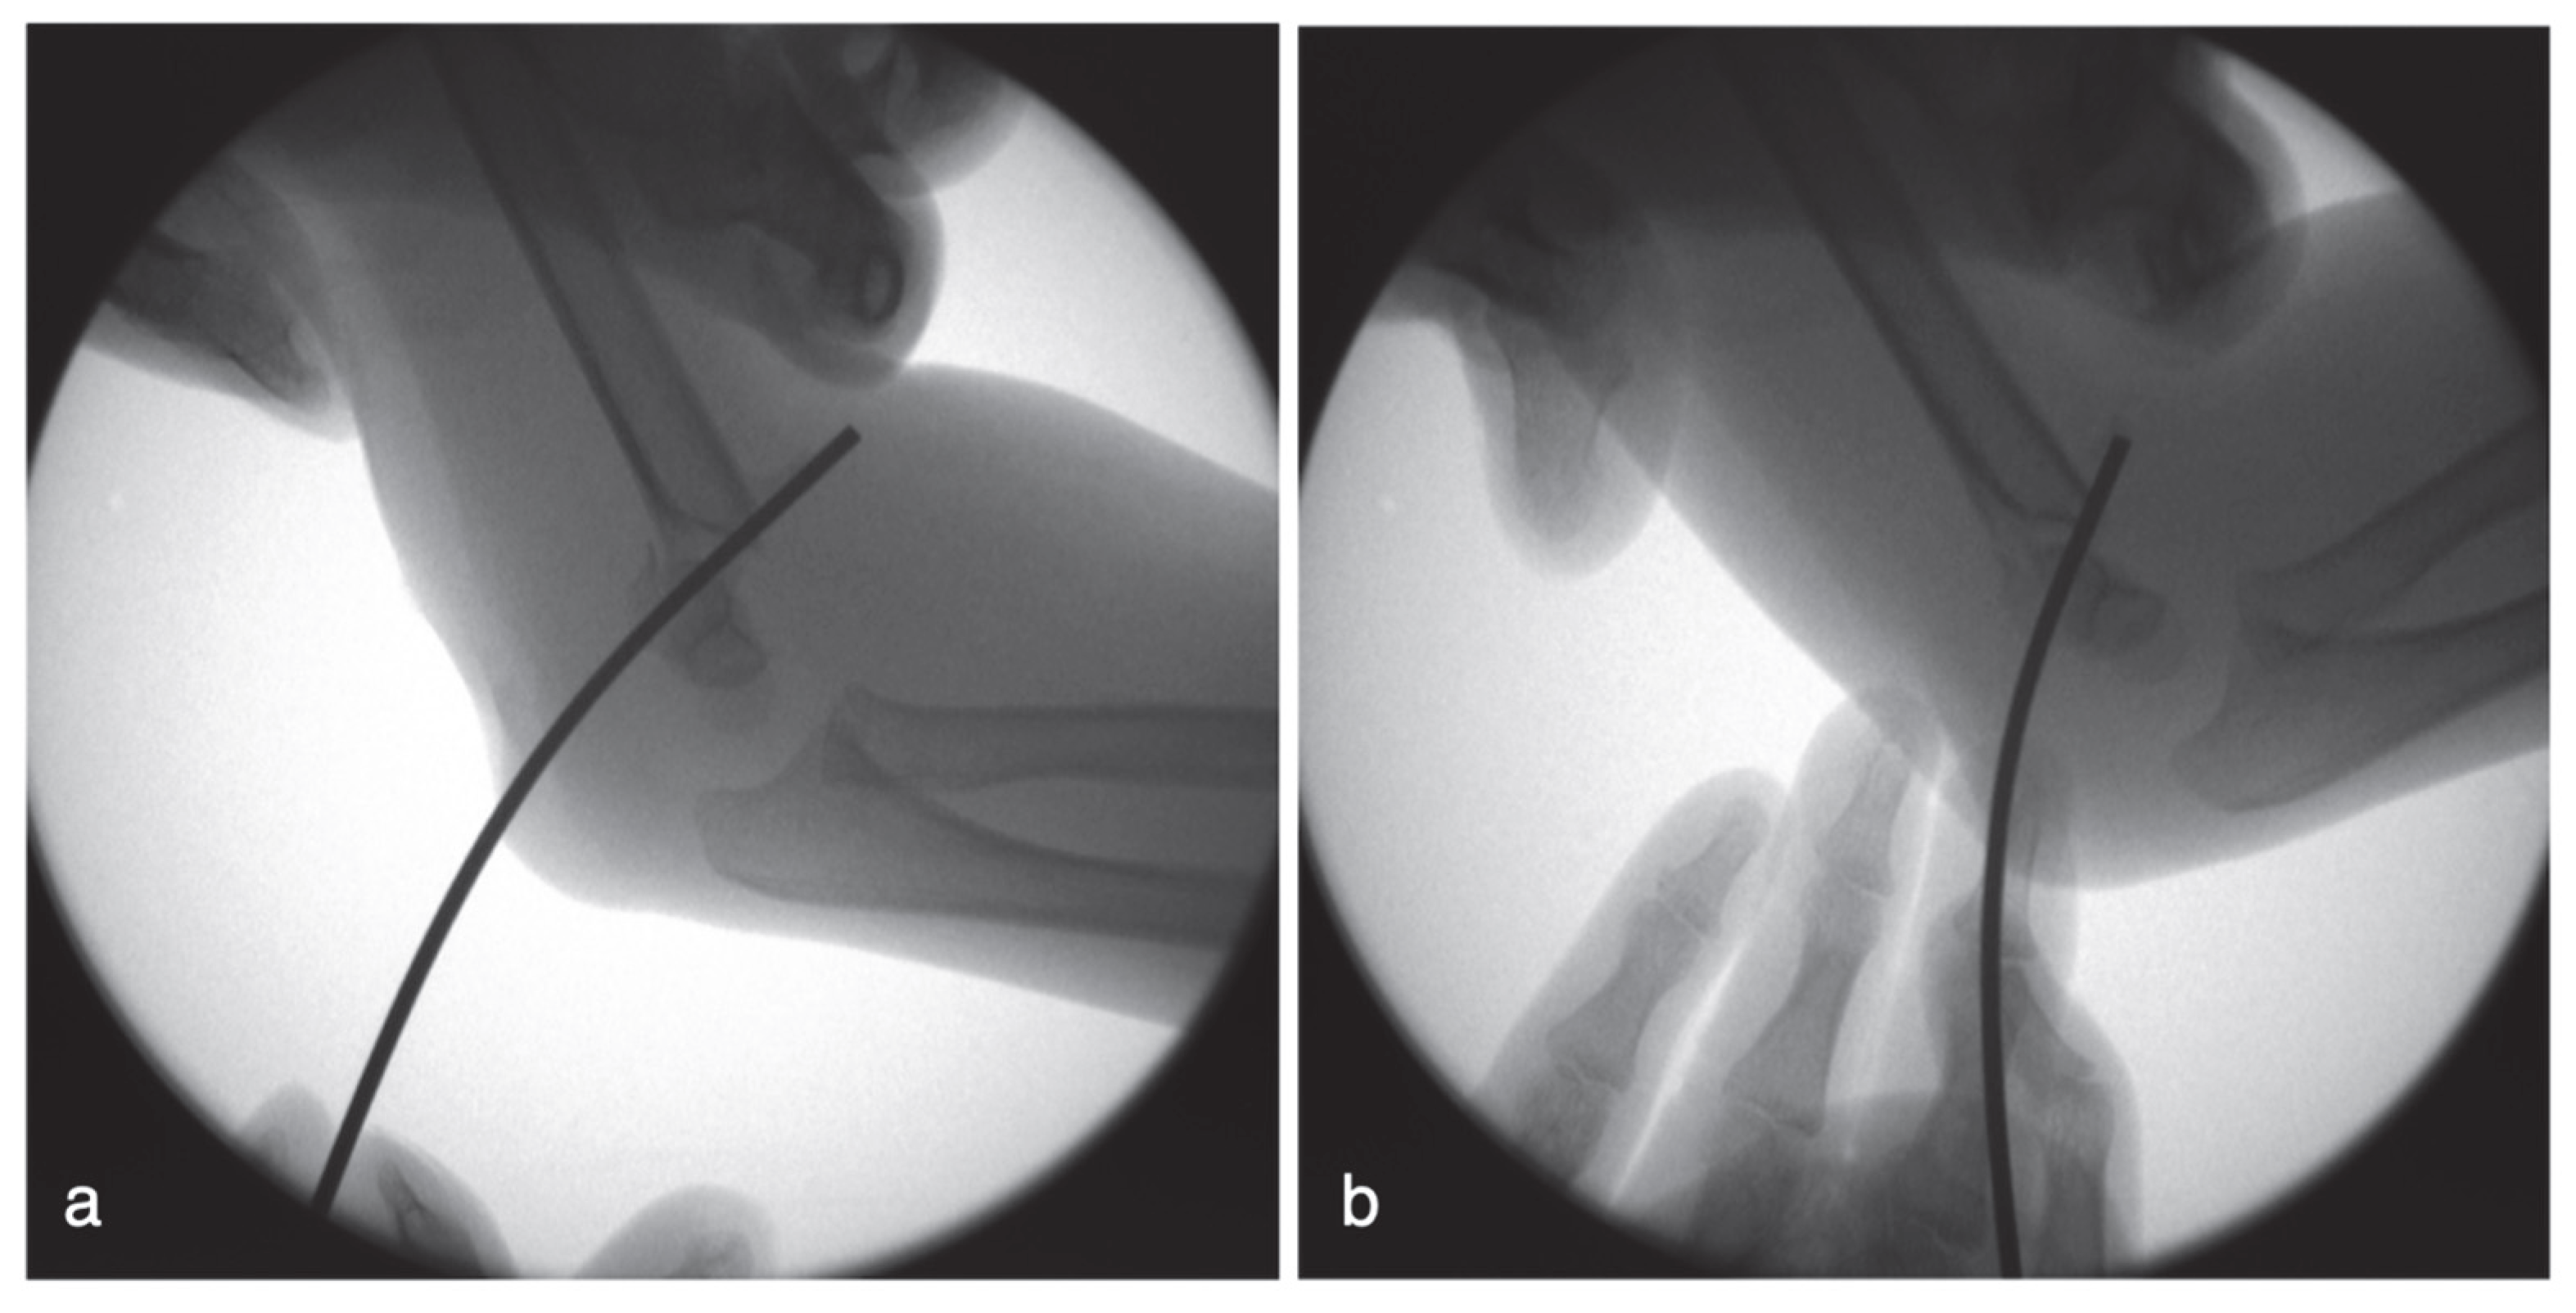

Figure 3a). After inserting the two lateral K-wires, we assessed fixation stability by flexing, extending, and rotating the elbow. If instability was observed (for example, relative displacement or angular change under C-arm fluoroscopy), we proceeded to place a medial pin. The elbow was then held in approximately 60° flexion. Because the lateral pins stabilized the fragments, mild extension maintained alignment and relaxed the ulnar nerve, reducing the risk of anterior subluxation (

Figure 3b). We identified the medial epicondyle by palpation. If swelling precluded palpation, we used C-arm fluoroscopy to confirm the positions of the medial epicondyle and the ulnar groove. A 1.6 mm smooth K-wire was secured in a universal chuck and held by the surgeon. The K-wire penetrated the skin over the medial epicondyle, and its tip was advanced toward the anteromedial aspect of the epicondyle. After the K-wire touched the bone, we verified the entry point under C-arm fluoroscopy. Care was taken not to insert the K-wire through the ulnar groove or the posterior aspect of the epicondyle (

Figure 3c) to limit the risk of ulnar nerve penetration or irritation. The cortex of the medial epicondyle was punctured after confirming the K-wire trajectory under image guidance. The wire was then advanced manually using oscillatory clockwise–counterclockwise rotation until bicortical fixation was achieved (

Figure 3d and

Figure 4).